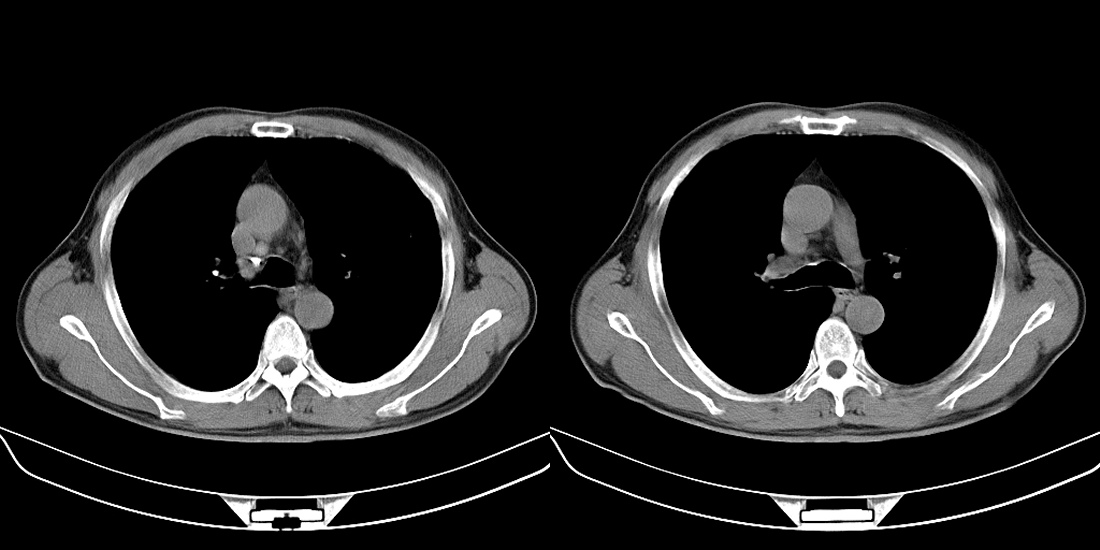

标题: CT10251:男性56岁,结核球? [打印本页]

标题: CT10251:男性56岁,结核球?

56岁男性,低热、消瘦,曾x线诊断肺结核。

两肺结核,左肺结核球。

双肺结核伴左上肺结核球形成